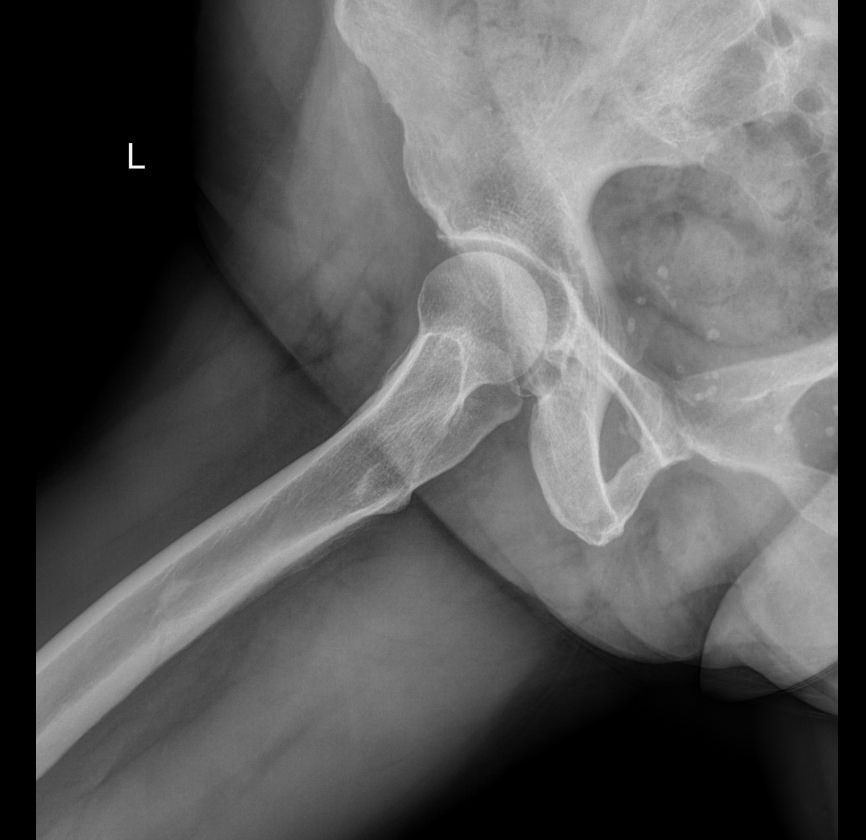

Рентгенография ― один из наиболее информативных методов диагностики патологий тазобедренных суставов. Это доступная, распространенная и неинвазивная диагностика, несущая минимальное количество ионизирующего излучения. В результате исследования можно обнаружить изменения, как травматические, так и воспалительного характера, происходящие с самыми крупными сочленениями костей в организме человека.

• Состояние суставных щелей, их симметричность и особенности;

• Соответствие вертлужных впадин головкам бедренных костей;

• Структуру костной ткани и патологические изменения в ней в области суставов;

• Врожденные аномалии, например, дисплазию;

• Переломы и вывихи;

• Новообразования.